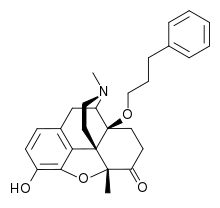

The pharmacodynamic response to an opioid depends upon the receptor to which it binds, its affinity for that receptor, and whether the opioid is an agonist or an antagonist. For example, the supraspinal analgesic properties of the opioid agonist morphine are mediated by activation of the μ1 receptor; respiratory depression and physical dependence by the μ2 receptor; and sedation and spinal analgesia by the κ receptor. Each group of opioid receptors elicits a distinct set of neurological responses, with the receptor subtypes (such as μ1 and μ2 for example) providing even more [measurably] specific responses. Unique to each opioid is its distinct binding affinity to the various classes of opioid receptors (e.g. the μ, κ, and δ opioid receptors are activated at different magnitudes according to the specific receptor binding affinities of the opioid). For example, the opiate alkaloid morphine exhibits high-affinity binding to the μ-opioid receptor, while ketazocine exhibits high affinity to ĸ receptors. It is this combinatorial mechanism that allows for such a wide class of opioids and molecular designs to exist, each with its own unique effect profile. Their individual molecular structure is also responsible for their different duration of action, whereby metabolic breakdown (such as N-dealkylation) is responsible for opioid metabolism.

Several semi-synthetic opioids were developed in Germany in the 1910s. The first, oxymorphone, was synthesized from thebaine, an opioid alkaloid in opium poppies, in 1914.[228] Next, Martin Freund and Edmund Speyer developed oxycodone, also from thebaine, at the University of Frankfurt in 1916.[229] In 1920, hydrocodone was prepared by Carl Mannich and Helene Löwenheim, deriving it from codeine. In 1924, hydromorphone was synthesized by adding hydrogen to morphine. Etorphine was synthesized in 1960, from the oripavine in opium poppy straw. Buprenorphine was discovered in 1972.[228]